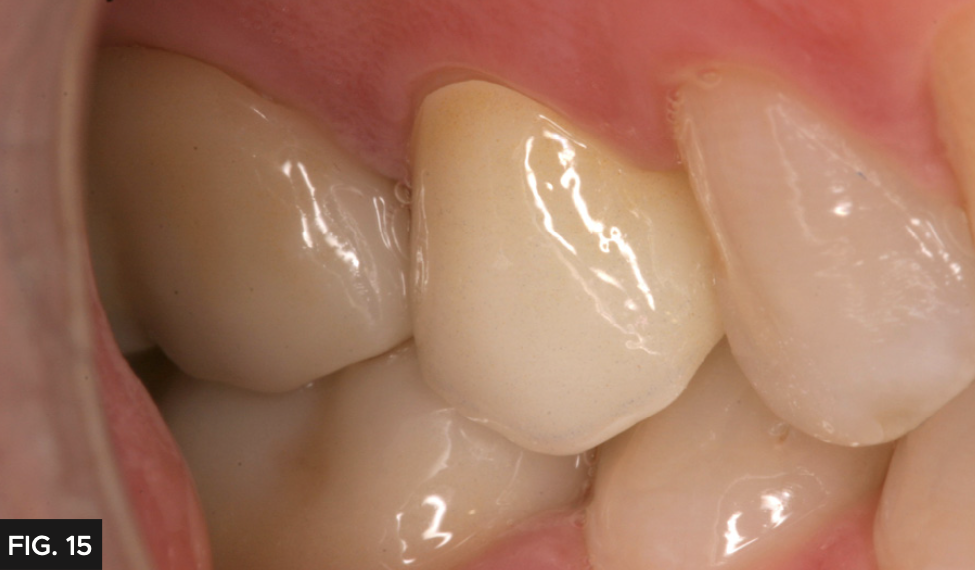

A 55-year-old patient presented to my office with tooth pain upon biting from his second bicuspid. Upon further examination a crack was noted on the mesial marginal ridge. (FIG. 1)